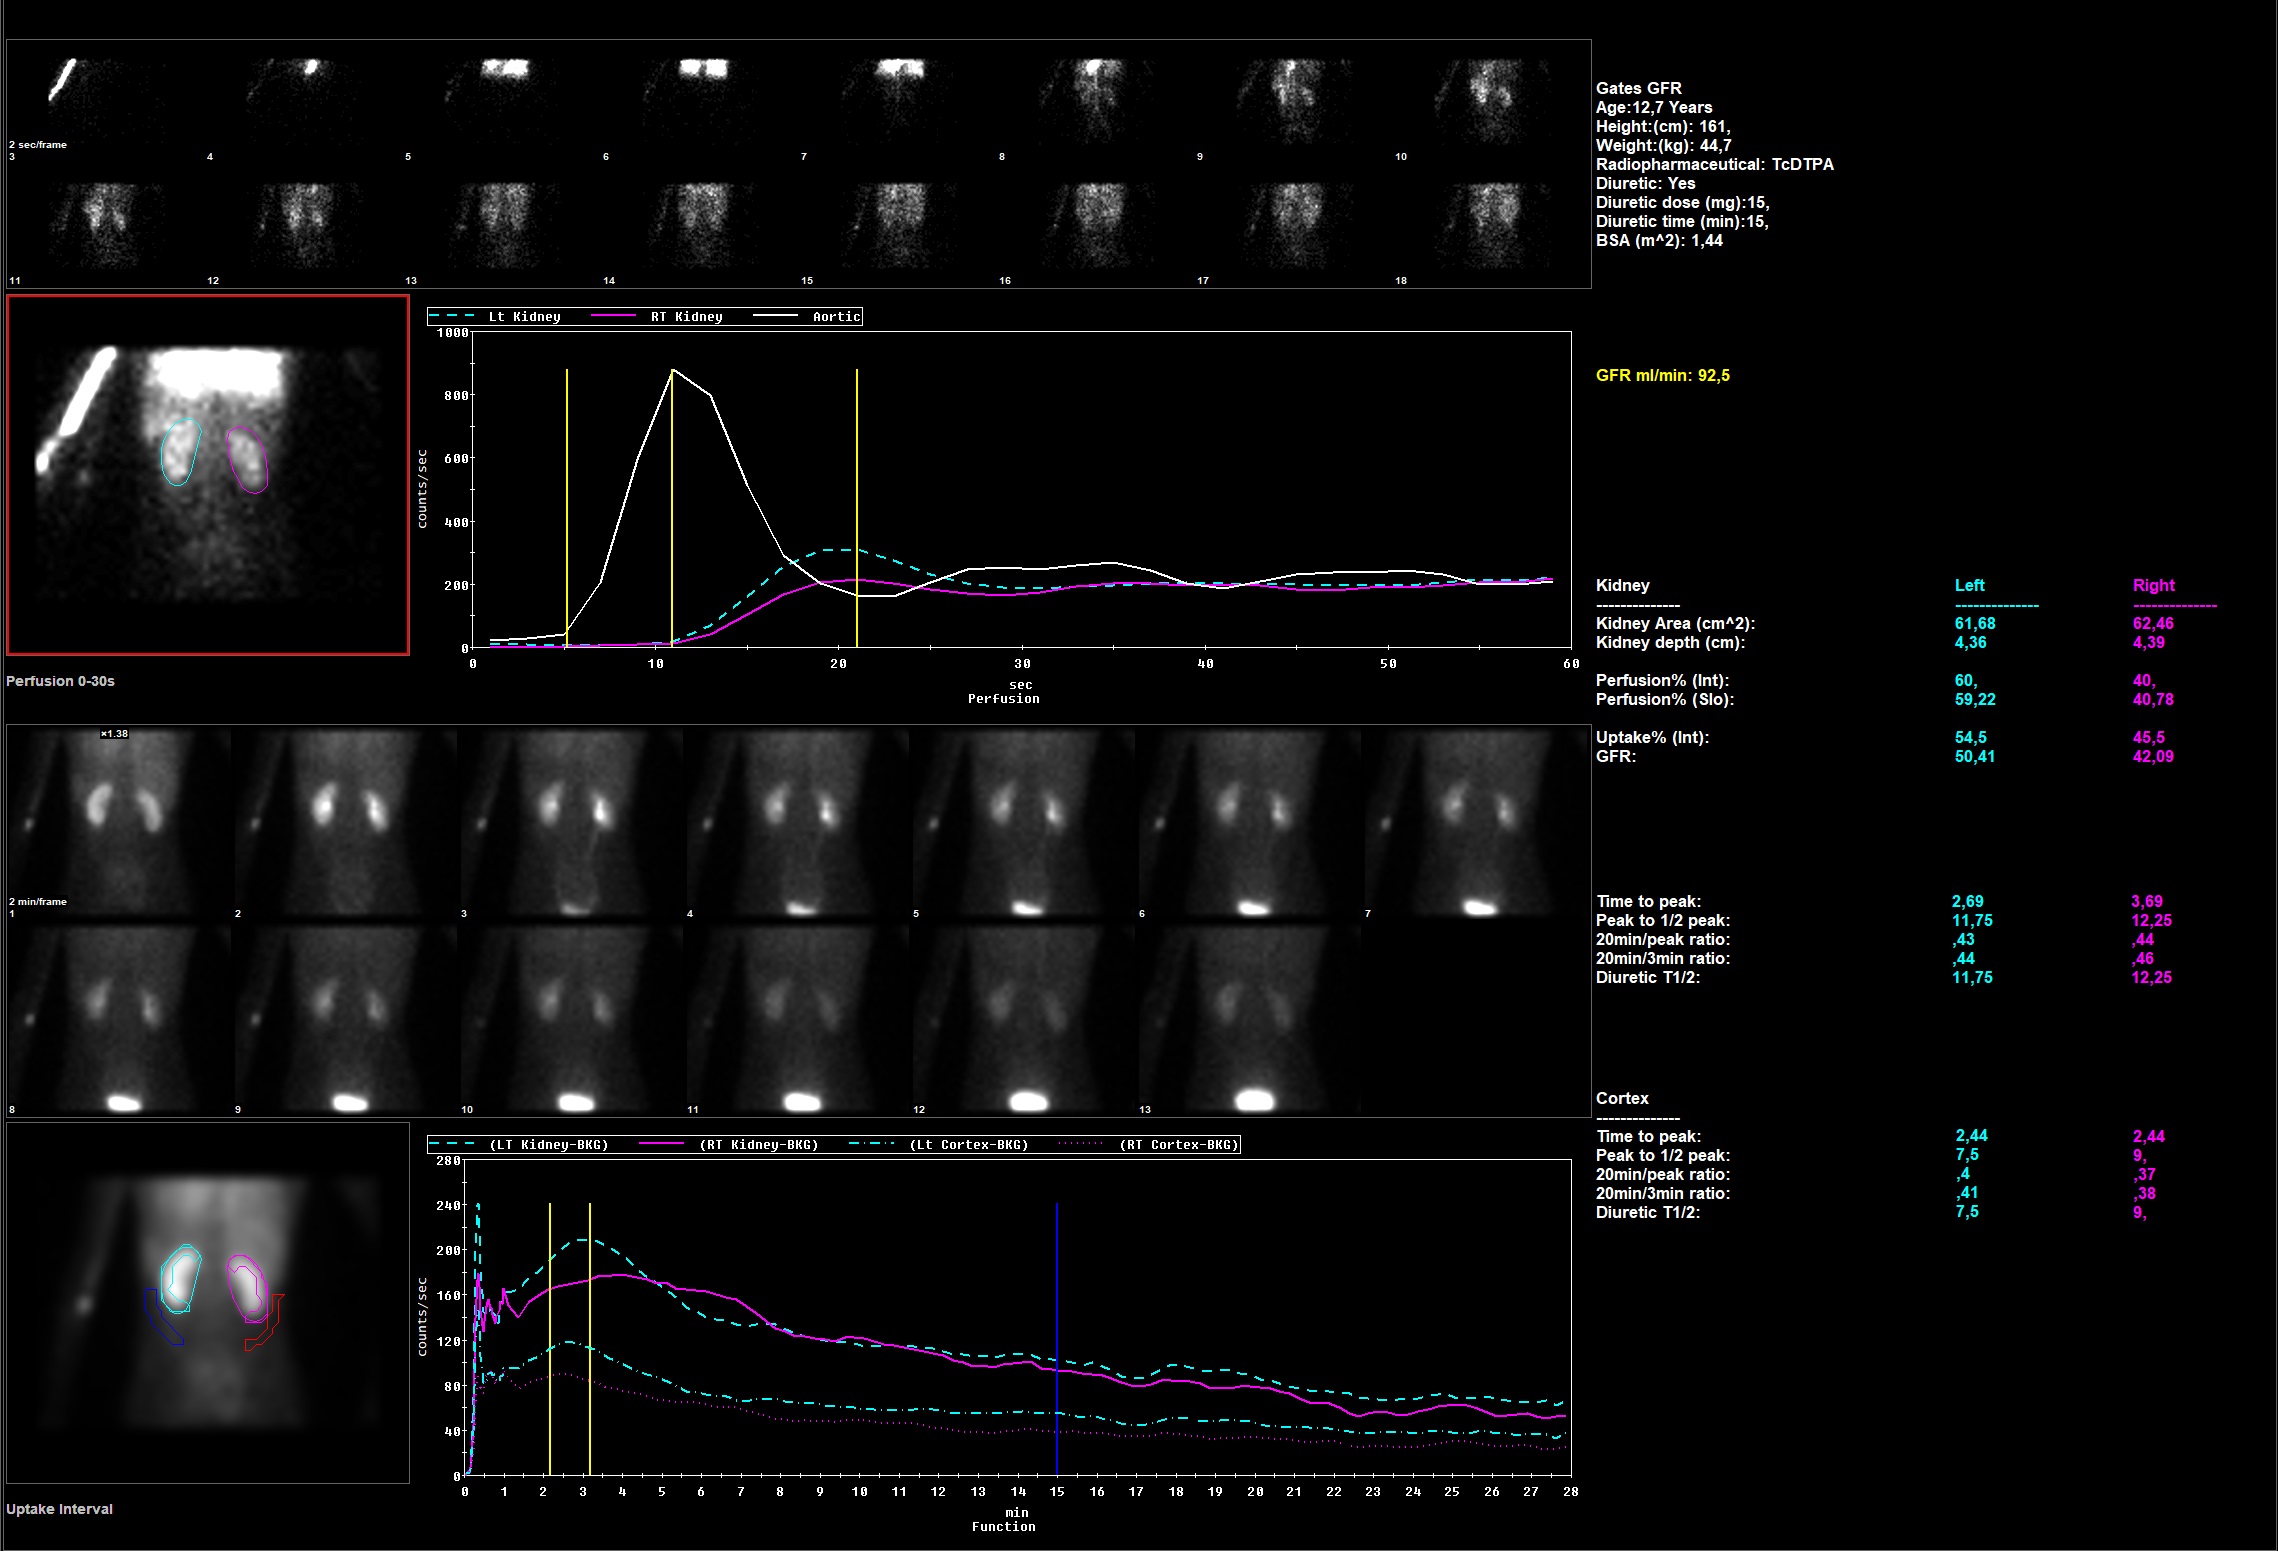

Tak. Badania radioizotopowe polegają na podaniu pacjentowi dożylnie związku chemicznego znakowanego radioizotopem – najczęściej technetem – i obserwowaniu, jak związek ten zachowuje się w organizmie: jak jest wychwytywany przez nerki i wydalany przez nie z moczem do pęcherza moczowego. Wspomniane badania to najczęściej scyntygrafia dynamiczna nerek lub scyntygrafia statyczna nerek.

Jak w każdym badaniu w medycynie nuklearnej, tak i w tych procedurach należy podać pacjentowi radiofarmaceutyk, czyli związek chemiczny znakowany radioizotopem promieniotwórczym 99mTc, który gromadzi się i/lub jest wydalany przez nerki. Rozkład podanego radiofarmaceutyku w nerkach, szybkość jego wydalania rejestrowane są z użyciem urządzeń o nazwie gamma kamera.

Badanie dynamiczne nerek to seria obrazów rejestrowanych przez ok. 25-30 minut w pozycji leżącej pacjenta. Uzyskane obrazy umożliwiają ocenę ilościową i jakościową czynności nerek, szybkość wydalania moczu, wartość przesączania kłębkowego i inne parametry ich funkcji. Badanie to ma zastosowanie u pacjentów z podejrzeniem nerkopochodnego nadciśnienia tętniczego, ale dodatkowo musi być wykonane badanie po podaniu kaptoprilu – leku który stosuje się też do leczenia nadciśnienia tętniczego. Inną zaletą badania dynamicznego nerek jest możliwość oceny zaburzeń w odpływie moczu z układu kielichowo-miedniczkowego, które występują często w przebiegu kamicy nerkowej u dorosłych lub wad wrodzonych u dzieci. Badania te są bardzo przydatne oraz bezpieczne nawet u bardzo małych dzieci: mogą być powtarzane, wykonywane w odstępie czasu, aby lepiej śledzić efekty leczenia na przykład operacyjnego. W wyniku badania uzyskuje się dane liczbowe, które umożliwiają porównanie czynności każdej z nerek w odstępie czasu.